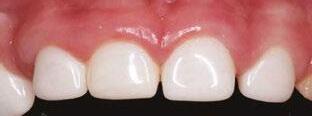

around these clinical sites. His anterior zirconia crowns showed healthy gingival margins with little-to-no plaque accumulations. This positive clinical finding is from the highly polished nature and biocompatibility of pediatric zirconia crowns. These restoration features limit plaque accumulations on the restoration and along the marginal gingiva, providing a localized positive aspect directly related to the choice of restorative material (Figure 2).

Case 2

A 3-year-old female presented with pulpal necrosis and abscess on #E and pulpal necrosis on #F. Extraction therapy or pulpectomy was offered. The family was highly motivated to retain #E and #F. The pulpectomy was performed with 0.02 K-Flex hand files, 3% NaOCl with a lateral vented needle, obturated with Vitapex (Neo Dental International Inc., Federal Way, Washington), a premixed paste of calcium hydroxide and iodoform. The access was filled with a HVGIC sealing the pulp therapy and increasing the clinical success by minimizing the potential for bacterial contamination. NuSmile ZR anterior crowns were selected as offering a full-coverage, esthetic, cemented restoration with no polymerization shrinkage when compared to a composite restoration. Crowns were cemented with NuSmile® BioCem (NuSmile, Houston, Texas). This is clinically beneficial as the provider would want to cement a restoration that provides limited microleakage minimizing the potential for bacterial contamination.15-17 At 6-month follow up, lesion healing had occurred with healthy gingival margins and no plaque accumulations (Figure 3).

Figure 3: NuSmile® ZR Crowns were selected as a cementable full coverage restoration. At 6-month recall, apical tissues were healed with excellent gingival health Figure 4: SMART style restorations that were definitively restored with NuSmile® ZR Crowns as an esthetic option to cover SDF staining